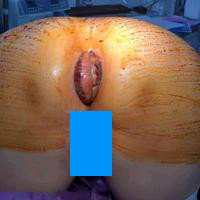

环状混合痔,大部分是血栓性外痔,广泛血栓

环状混合痔,大部分是血栓性外痔,广泛血栓形成,内痔稍脱出。手术方式如何选择。横断式切除还是成形。 下周我在发布术后恢复照片。...